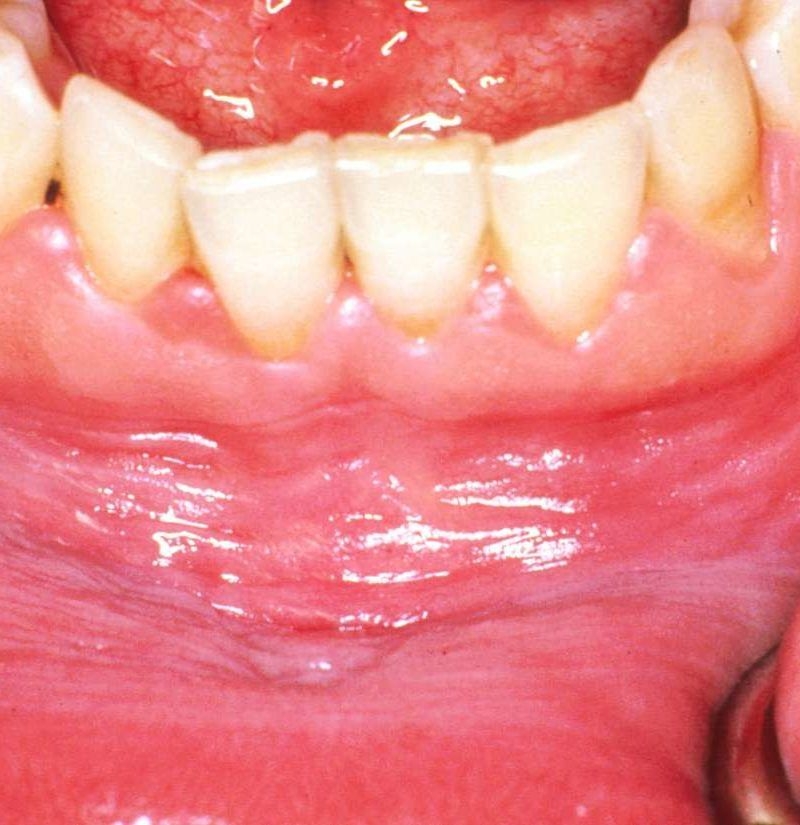

White dots on gums can be caused by a variety of factors, including canker sores, oral thrush, or even oral cancer. Canker sores are small, painful ulcers that can develop on the gums and other areas of the mouth. Oral thrush is a fungal infection that can also cause white patches on the gums. In more severe cases, white dots on gums can be a symptom of oral cancer, which requires immediate medical attention.

Treatment for white dots on gums may vary depending on the cause. For canker sores, over-the-counter medications or mouth rinses can help alleviate pain and promote healing. Oral thrush may require antifungal medications prescribed by a healthcare provider. In cases of oral cancer, treatment options may include surgery, radiation therapy, or chemotherapy.